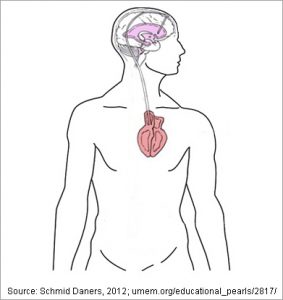

Shunts are medical devices used to treat hydrocephalus, a condition in which excess cerebrospinal fluid (CSF) builds up in the brain. A shunt system helps redirect this fluid from the brain’s ventricles to another area of the body—most often the abdominal cavity—where it can be safely absorbed.

This device drains cerebrospinal fluid from the brain to the abdominal cavity with a thin silicone tube. A valve is used to control the amount of fluid drained.

Additionally, patients who already have VP shunts but need further drainage to achieve symptom relief may need to drain directly into the lower pressure venous vessels. This is achieved with a ventriculoatrial shunt (VA Shunt).